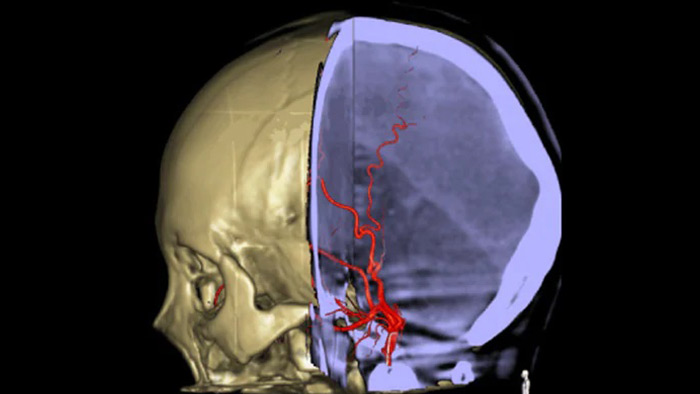

CT-like visualization of soft tissue, bone and vascular structures.

SmartCT Soft Tissue is an X-ray acquisition technique that generates a CT-like visualization of soft tissue in relation to other structures during procedures – all controlled via the touch screen at the table. You can use the CT-like imagesto assess soft tissue, bone structure and stent deployment before, during and after interventional procedures.

SmartCT Vaso provides high resolution 3D imaging that reveals key information about cerebral vascular structures to support the highest possible spatial assessment of vessels in the soft tissue context.